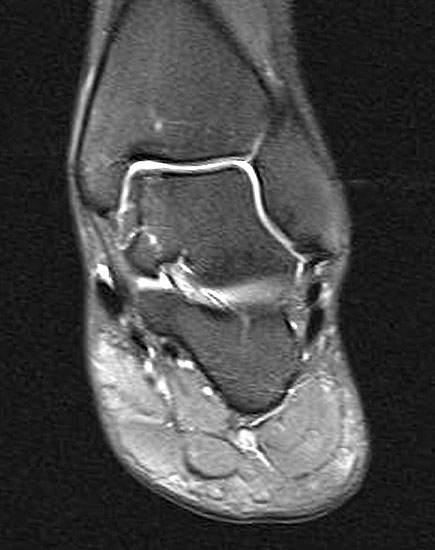

Abbildung 1: Osteochondrale Läsion der medialen Talusschulter mit subchondralem Begleitödem und Zyste.

Abbildung 1

• MRT des Sprunggelenks zur Beurteilung der Knorpelläsion, möglichen subchondralen Zysten, nekrotischen Knochenarealen und anderen Begleitpathologien (Abbildung 1).

Die Darstellung der weiteren Operationstechnik erfolgt am Beispiel eines medialen Zugangs bei einer Osteochondrosis dissceans mit subchondraler Zyte der medialen Talusschulter (siehe MRT Abbildung 1).